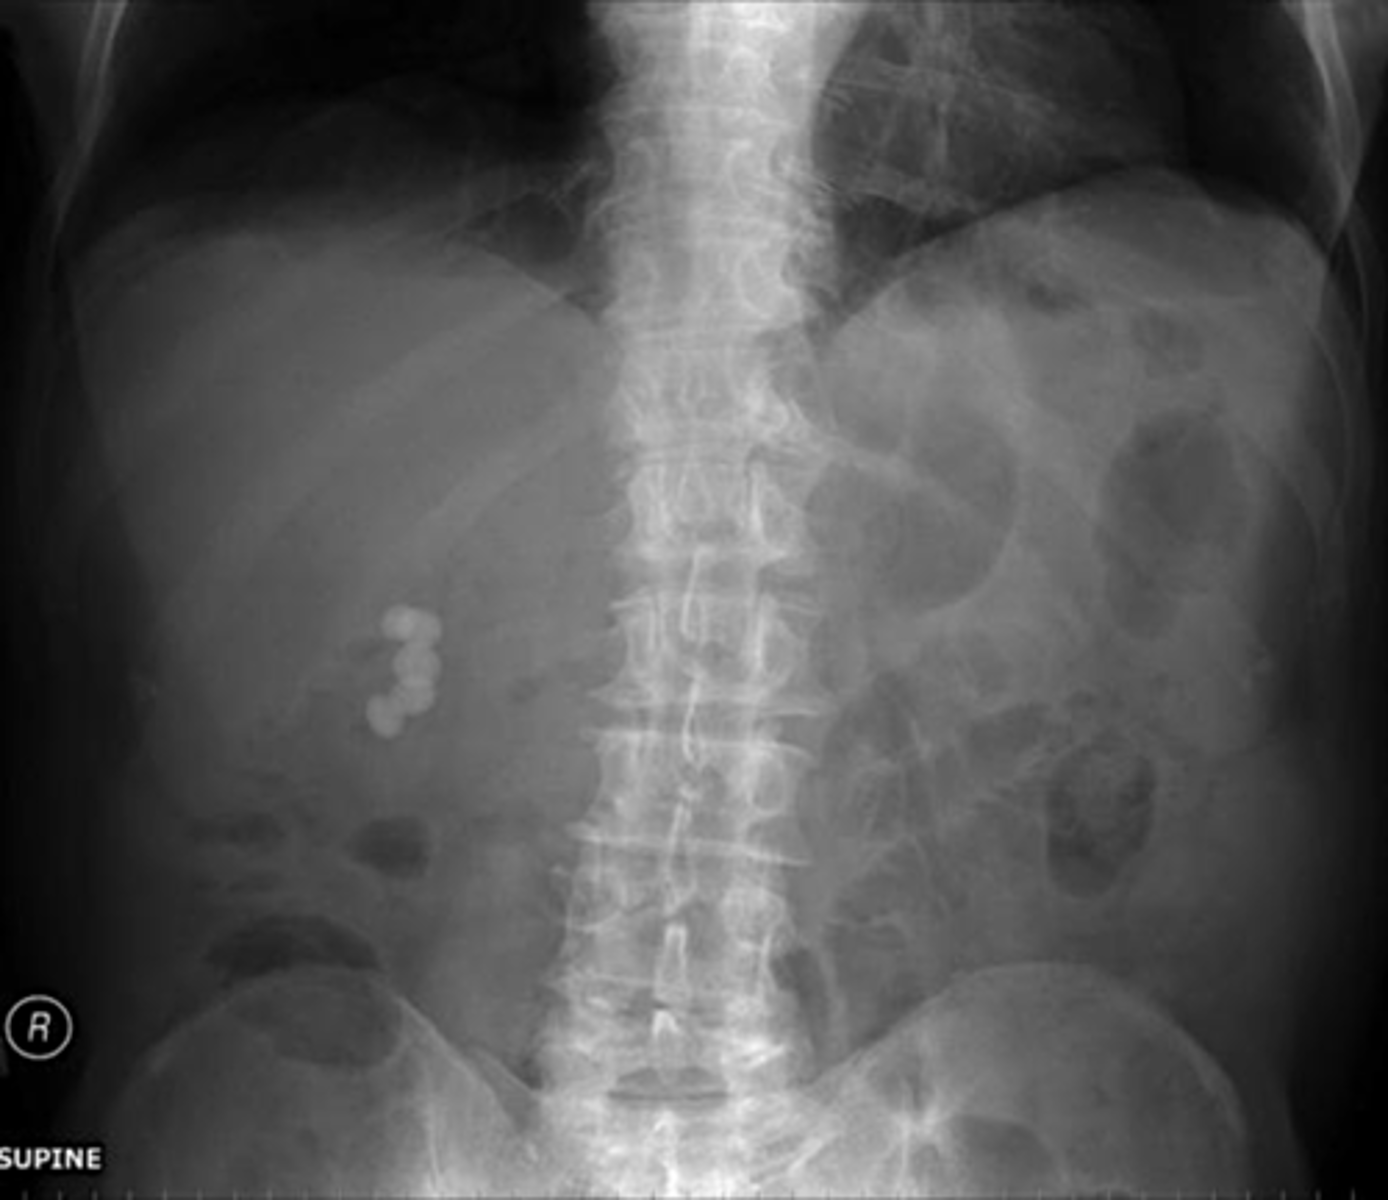

Gallstones

Gallstones (pic 2)

Gallstones (pic 3)

Gallstones (pic 4)